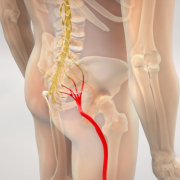

Quando la propriocezione non funziona bene

Quando questo sistema è alterato:

- il movimento perde precisione

- aumentano i compensi

- cresce lo sforzo

- aumentano le co-contrazioni (spasticità e contratture)

- dimuisce la forza che si può esprimere

- si perde coordinazione

👉 Questo può influenzare sia la vita quotidiana che l’attività sportiva.

🔸 Riabilitazione

- recupero del movimento

- riduzione dei compensi

Agire sulla propriocezione per agire sul controllo motorio.

👉 La propriocezione è la rete nervosa costituita da una miriade di sensori e neuroni che raccoglie ed elabora le informazioni necessarie a gestire e ottimizzare il movimento